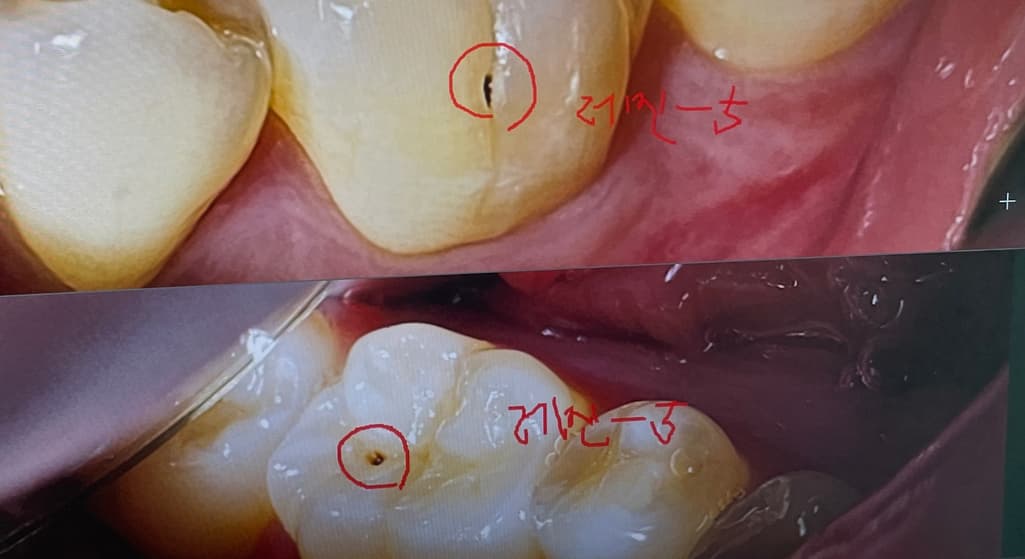

사진에 보이는 충친는 진행되고 잇는 충치같아서 간단히 충치를 제거하고 레진으로 떼우시는게 좋을것같습니다.

사진으로 보이는 충치는 치아 표면에 구멍이 나있으며 시간이 지나면서 안쪽으로 진행되어 가는 충치로 보입니다.

시간이 지나면 내부로 충치가 더 진행될수 있기때문에 가능하면 빠르게 치료하는것이 좋을것으로 생각됩니다.

큰 충치는 아니나 구멍으로 음식물이 껴서 잘 안빠지면 그게 충치를 더 크게 만들기 때문에 치료해줘도 좋을 단계입니다